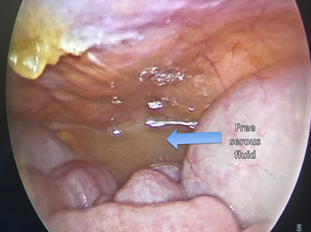

Laboratory tests showed: Hemoglobin: 13.2g/dl, Hematocrit: 41.3%, Leucocytes: 7.8103/L, Bands: 2%, Platelet: 353103/L, BUN: 14.2mg/dl, Creatinine: 0.83mg/dl, Na: 12meq, K: 3.80meq, Cl: 108meq, Ca: 6.60meq, P: 3.29meq, Albumin: 4g/dl, AST: 23U/L, ALT: 12U/L, Alkaline phosphatase: 91U/L, LDH: 244U/L, Amylase: 265U/L, Lipase: 11U/L. Plain abdominal and chest X-rays showed acute gastric dilatation and massive pneumoperitoneum (Figures 1&2). Due to the medical and surgical history which included chronic use of NSAIDs, as well as her symptoms, physical exam and imaging studies, the suggestive diagnosis of hollow viscus perforation was made, so an exploratory laparoscopy was performed to address the problem. Laparoscopic inspection of the abdominal cavity, revealed free serous fluid in the pelvic cavity without evidence of sepsis or intestinal fluid (Figure 3). A dilated stomach without obvious perforation and gas infiltration in lesser omentum was observed (Figures 4&5). An exhaustive review was carried out throughout the small bowel from Treitz ligament to the ileocecal valve and the entire colon length to rule out possible sites of perforation, without finding any evidence of it. Aspiration of the liquid and thorough irrigation of the abdominal cavity with saline solution was performed, and finally drainage was placed in the subhepatic space. Postoperative course was uneventful. She was started on liquids at 48hs after surgery, the drainage was removed and she was discharged on the fifth day after the surgical procedure. She was seen at the office several times after this event. Currently she lives a normal life, without restrictions secondary to this episode.

Figure 1 Massive gastric dilatation and free intra-abdominal air.

Figure 3 Free serous fluid in the pelvic cavity.